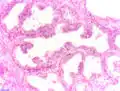

97 % aller Prostatatumoren sind Adenokarzinome, das heißt, sie entstehen aus entarteten Drüsenzellen. Ein Übergangsstadium zum manifesten Krebs wird als prostatische intraepitheliale Neoplasie (PIN) bezeichnet und entspricht einem Carcinoma in situ. Beim eigentlichen Karzinom kommen verschiedene histopathologische Wachstumsmuster vor, auch gleichzeitig nebeneinander: glandulär beziehungsweise azinär (drüsenartig), kribriform (siebartig) und solide. Das Ausmaß der Entdifferenzierung ist Grundlage des Gradings. 40–50 % der Tumoren liegen bei Diagnosestellung multifokal vor.[54]

Prostatische intraepitheliale Neoplasie (PIN)

Prostatische intraepitheliale Neoplasie (PIN) -